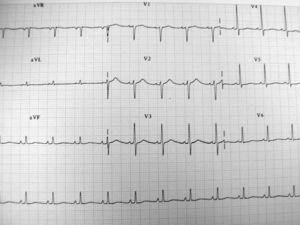

Figura 1. Electrocardiograma al ingreso en el Servicio de Urgencias.

Presentamos el caso de un paciente de 41 años que llevó a cabo una ingesta voluntaria de un producto de limpieza industrial con intención autolítica. Fue recibido en el Servicio de Urgencias transcurridas 5 horas de la ingesta del tóxico. A su llegada destacaba la existencia de hipotensión arterial (presión arterial [PA]: 90/60 mmHg) que fue refractaria a la administración de fluidoterapia en forma de cristaloides. Así mismo, presentaba importante disnea, requiriendo aporte de oxígeno a alto flujo. Entre las pruebas diagnósticas realizadas destacó únicamente la existencia de acidosis metabólica en la gasometría arterial (pH: 7,32, pCO2: 34, pO2: 75, EB:-11). Tanto la radiografía de tórax como el electrocardiograma (ECG) fueron normales (fig. 1). Ante la inestabilidad del paciente se decidió su traslado a la Unidad de Cuidados Intensivos (UCI), e ingresó en dicha Unidad transcurridas 7 horas de la ingesta del tóxico. Dada la persistencia de hipotensión arterial se realizó reposición de fluidos con coloides y cristaloides y conjuntamente se inició tratamiento con aminas vasoactivas. Se extrajo analítica básica, con gasometría arterial y venosa, radiografía de tórax y ECG. En el ECG se objetivó la presencia de un ritmo sinusal a 105 latidos por minuto con un intervalo QT alargado (fig. 2). Unos minutos después de su llegada a la UCI el paciente presentó parada cardiorrespiratoria súbita secundaria a fibrilación ventricular. Se llevó a cabo desfibrilación, siendo necesarios un total de tres choques eléctricos (200J, 200J y 360J), tras los cuales el paciente recuperó el ritmo cardíaco en forma de taquicardia sinusal. Se procedió a su intubación y conexión a ventilación mecánica. El episodio se repitió en otras dos ocasiones, respondiendo en ambos casos a una serie de tres choques eléctricos respectivamente, bolo de 1 mg de adrenalina endovenosa y lidocaína en bolo de 1 mg/kg de peso y posterior perfusión continua a razón de 3 mg/minuto. Posteriormente se observó en la analítica extraída a su ingreso en UCI la existencia de unos niveles séricos de calcio de 4,6 mg/dl. Se procedió a reposición del mismo siendo necesaria igualmente la administración de noradrenalina y dobutamina en perfusión endovenosa. No se produjeron nuevos episodios de fibrilación ventricular. En los días sucesivos presentó insuficiencia renal anúrica que requirió de hemodiafiltración venovenosa continua. Así mismo, desarrolló un cuadro de deterioro neurológico en situación de estado vegetativo persistente, con una puntuación en la escala de coma de Glasgow de 8 puntos. Se realizó tomografía axial computarizada (TC) craneal sin hallazgos significativos y electroencefalograma compatible con encefalopatía difusa en grado moderado-severo. Fue dado de alta de la UCI tras 32 días de estancia y previa realización de traqueotomía percutánea. Permaneció en planta de hospitalización durante un período de 10 días, falleciendo finalmente como consecuencia de una complicación de naturaleza infecciosa.